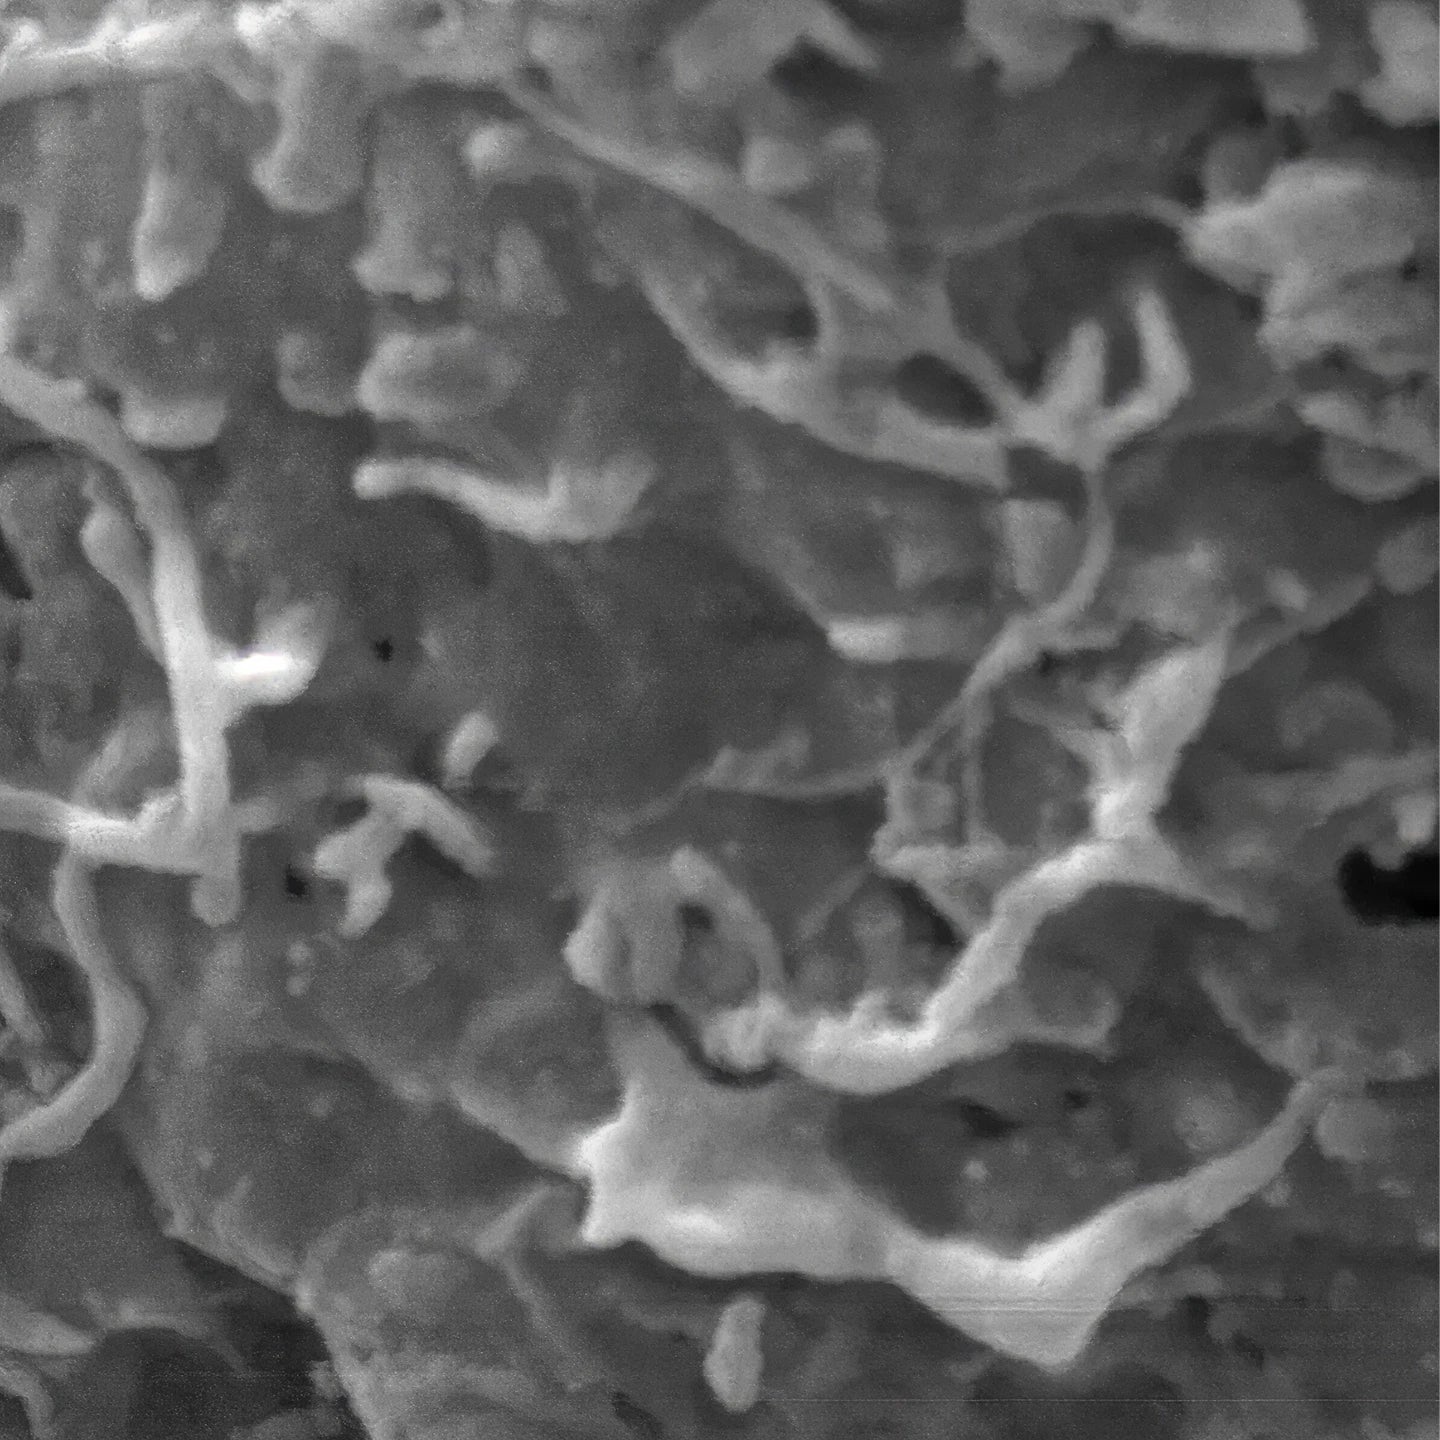

Collagen fiber network at baseline before (a) and after 12-week intake of the oral collagen supplementation (b).

Reference: Dähnhardt, D., Dähnhardt-Pfeiffer, S., Segger, D. et al. Restoration of the Ultrastructural Integrity

of the Dermal Collagen Network by 12-Week Ingestion of Special Collagen Peptides. Dermatol Ther

(Heidelb) 14, 2509–2521 (2024). https://doi.org/10.1007/s13555-024-01251-8